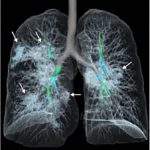

Vedi anche: COVID 19: TAC e radiografie potrebbero sostituire i test virali per lo screening e la diagnosi?